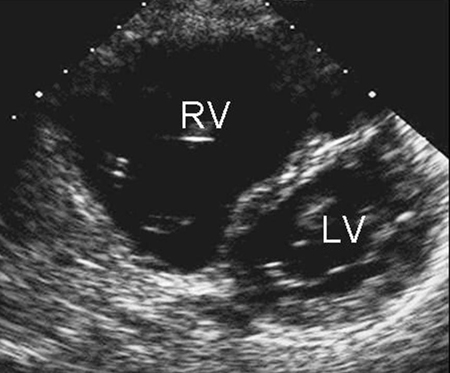

Imagen de ecocardiografía de eje corto paraesternal que demuestra agrandamiento ventricular derecho en un paciente con una comunicación interauricular (CIA). (VD) ventrículo derecho; (VI) ventrículo izquierdo